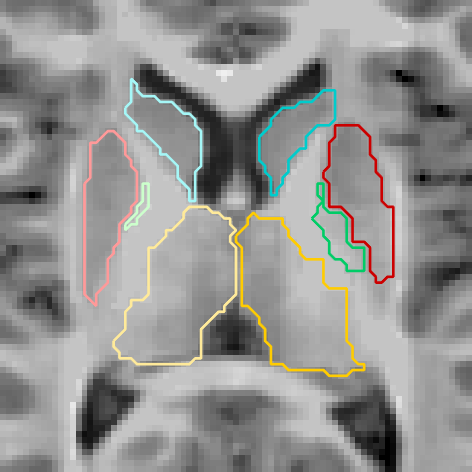

Figures 6 and 3.2 give visual examples of segmentations obtained by our 3D FCNN architecture and standard references contoured by FreeSurfer.

It can be observed that the segmentations generated by our proposed architecture are significantly smoother than those of FreeSurfer, regardless of the subject group (i.e diagnosis, age, site employed or not in training). We also notice that our system is better at identifying thin regions in the structures of interest, for instance, the lower extremities of pallidum (green regions).

Site NOT used in training

Figure 7: Visual examples of our 3D FCNN architecture compared with the references standard contoured by FreeSurfer for three test subjects from sites not used in training.